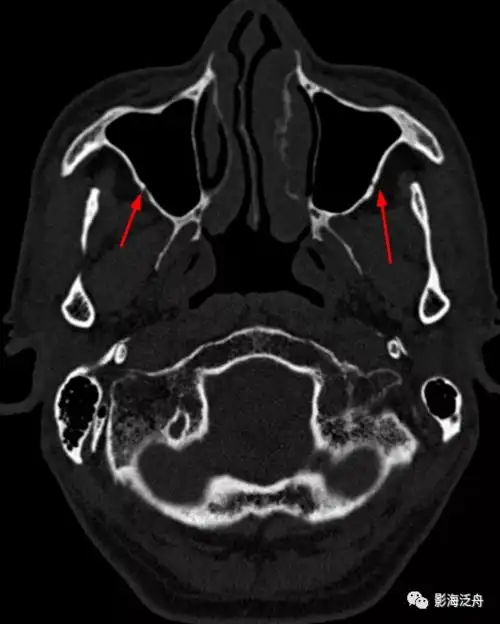

颞下颌关节检查

颞骨ct 水平位

图文并茂▏颞骨正常ct解剖

颞下颌关节紊乱病(tmd) 涉及科室:口腔科,口腔医院 检查优势 ct

夜班不求人颅骨骨折下